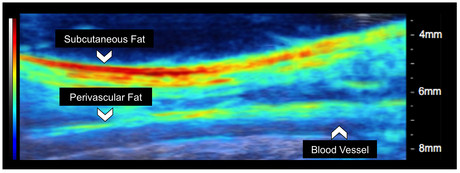

Photoacoustic tomography is a non-invasive technique that works by converting absorbed optical energy into an acoustic signal. Pulsed light is sent into body tissue, creating a small increase in temperature that causes the tissue to expand and create an acoustic response that can be detected by an ultrasound transducer. The ultrasound data is used to visualise the tissue.

Now, Goergen and his colleagues have developed an adjustable photoacoustic probe that is said to feature improved light delivery and image quality, described in the journal Photoacoustics. The system provides real-time compositional information of body tissue without the need for contrast agents and with better depth penetration compared with conventional optical techniques.

One of the challenges of photoacoustic tomography is improving the penetration depth and signal-to-noise ratio past optical absorbers. The researchers believe creating optical manipulation techniques to maximise photon density could provide a solution. As a result, they have created a motorised photoacoustic holder that allows users to easily manoeuvre the aim of the device and tune the depth where light is focused, improving the light penetration depth and signal-to-noise ratio.